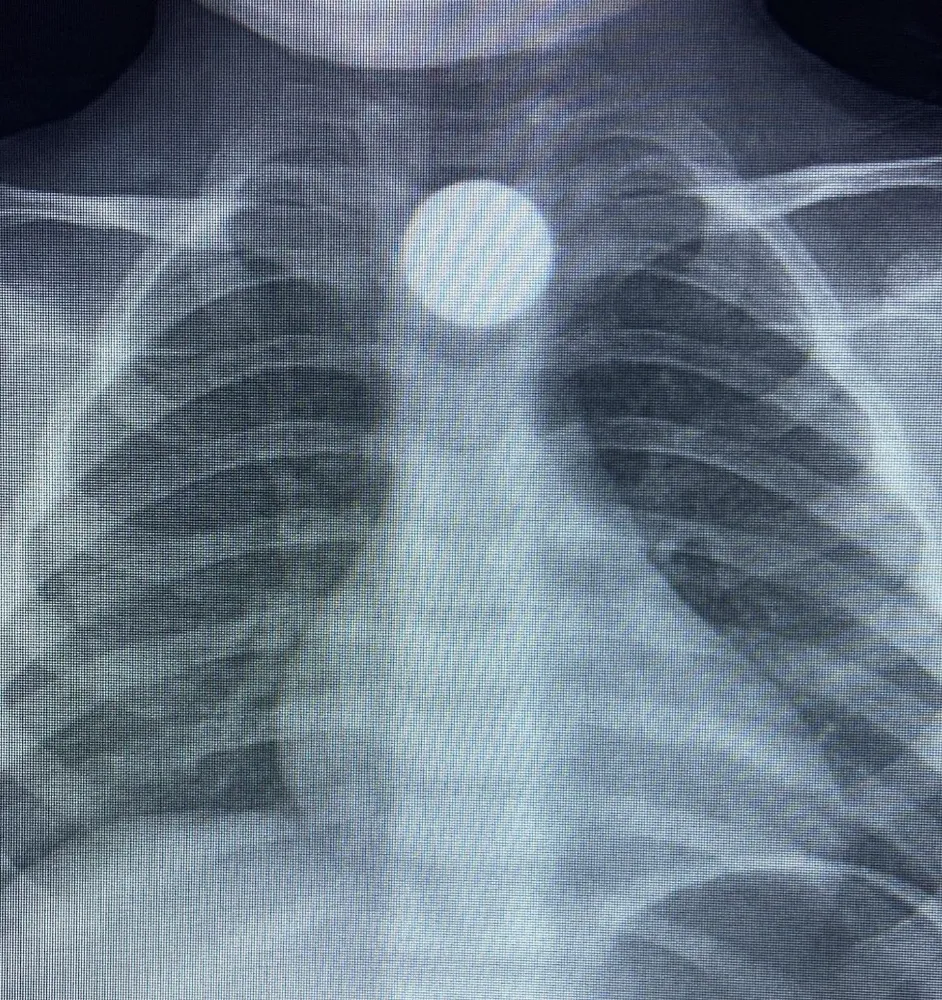

Olay, kırsal Yeniceköy Mahallesi’nde meydana geldi. Bilal K., evde oynarken yerde bulduğu 50 kuruş madeni parayı ağzına alıp yuttu. Durumu fark eden ailesi, Bilal K.’yi özel araçla İnegöl Devlet Hastanesi’ne götürdü. Hastanede yapılan kontrollerde, madeni paranın Bilal K.’nin yemek borusunda takılı kaldığı belirlendi. Burada ilk müdahalesi yapılan Bilal K., daha sonra ambulansla Bursa Yüksek İhtisas Eğitim ve Araştırma Hastanesi’ne sevk edildi.

Bilal K.’nin tedavisinin sürdüğü öğrenilirken, olaya ilişkin soruşturma başlatıldı.